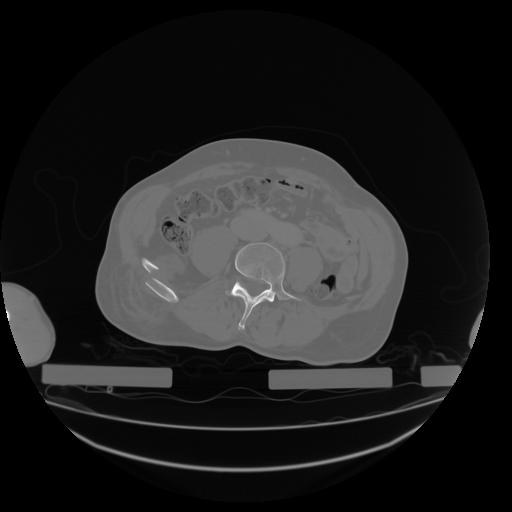

27 CUERPO,CE,Axial,3.0,CUERPO,,